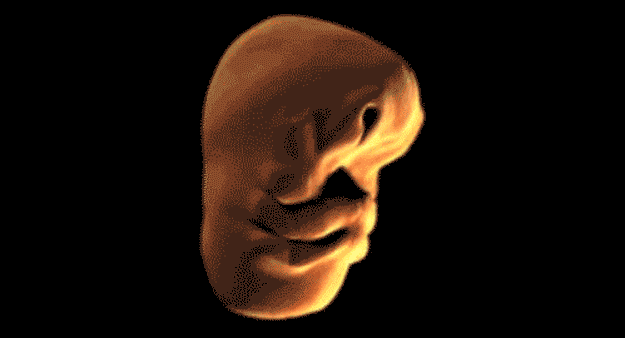

Cum se formează faţa unei persoane în pântecul mamei